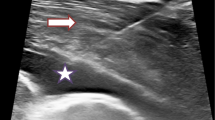

The introduction of a histopathologic grading system for epithelioid PM in the 2021 WHO classification is a significant development in PM pathology reporting, with nuclear grade linked to overall survival [8••] (See Fig. 1). First proposed in 2012, the three tier grading system was developed using a predominantly surgical population [16]. The system assigns a score of 1–3 for both nuclear atypia and mitotic count at histological analysis. Scores are combined to produce the three-tier grade, which was an independent predictor of survival. During validation in another predominantly surgical cohort, the presence or absence of necrosis added further prognostic value [4]. Necrosis was combined with three-tier grade to form the two-tier nuclear grade.

Both scores were externally validated in non-surgical biopsy samples [17]. Median survival was 8.9 months in high nuclear grade and 19.3 months in low grade. The prognostic relationship disappeared with smaller biopsies, highlighting the importance of biopsy size and number when assessing nuclear grade [17]. This is likely to reflect the histological heterogeneity of PM tumours, requiring multiple large samples from different tumour sites to increase the chance of representative sampling.

Reporting of nuclear grade is now recommended for all epithelioid PM tumours at diagnosis [4]. The prognostic information it provides can help patients and clinicians share decision making when planning treatment.